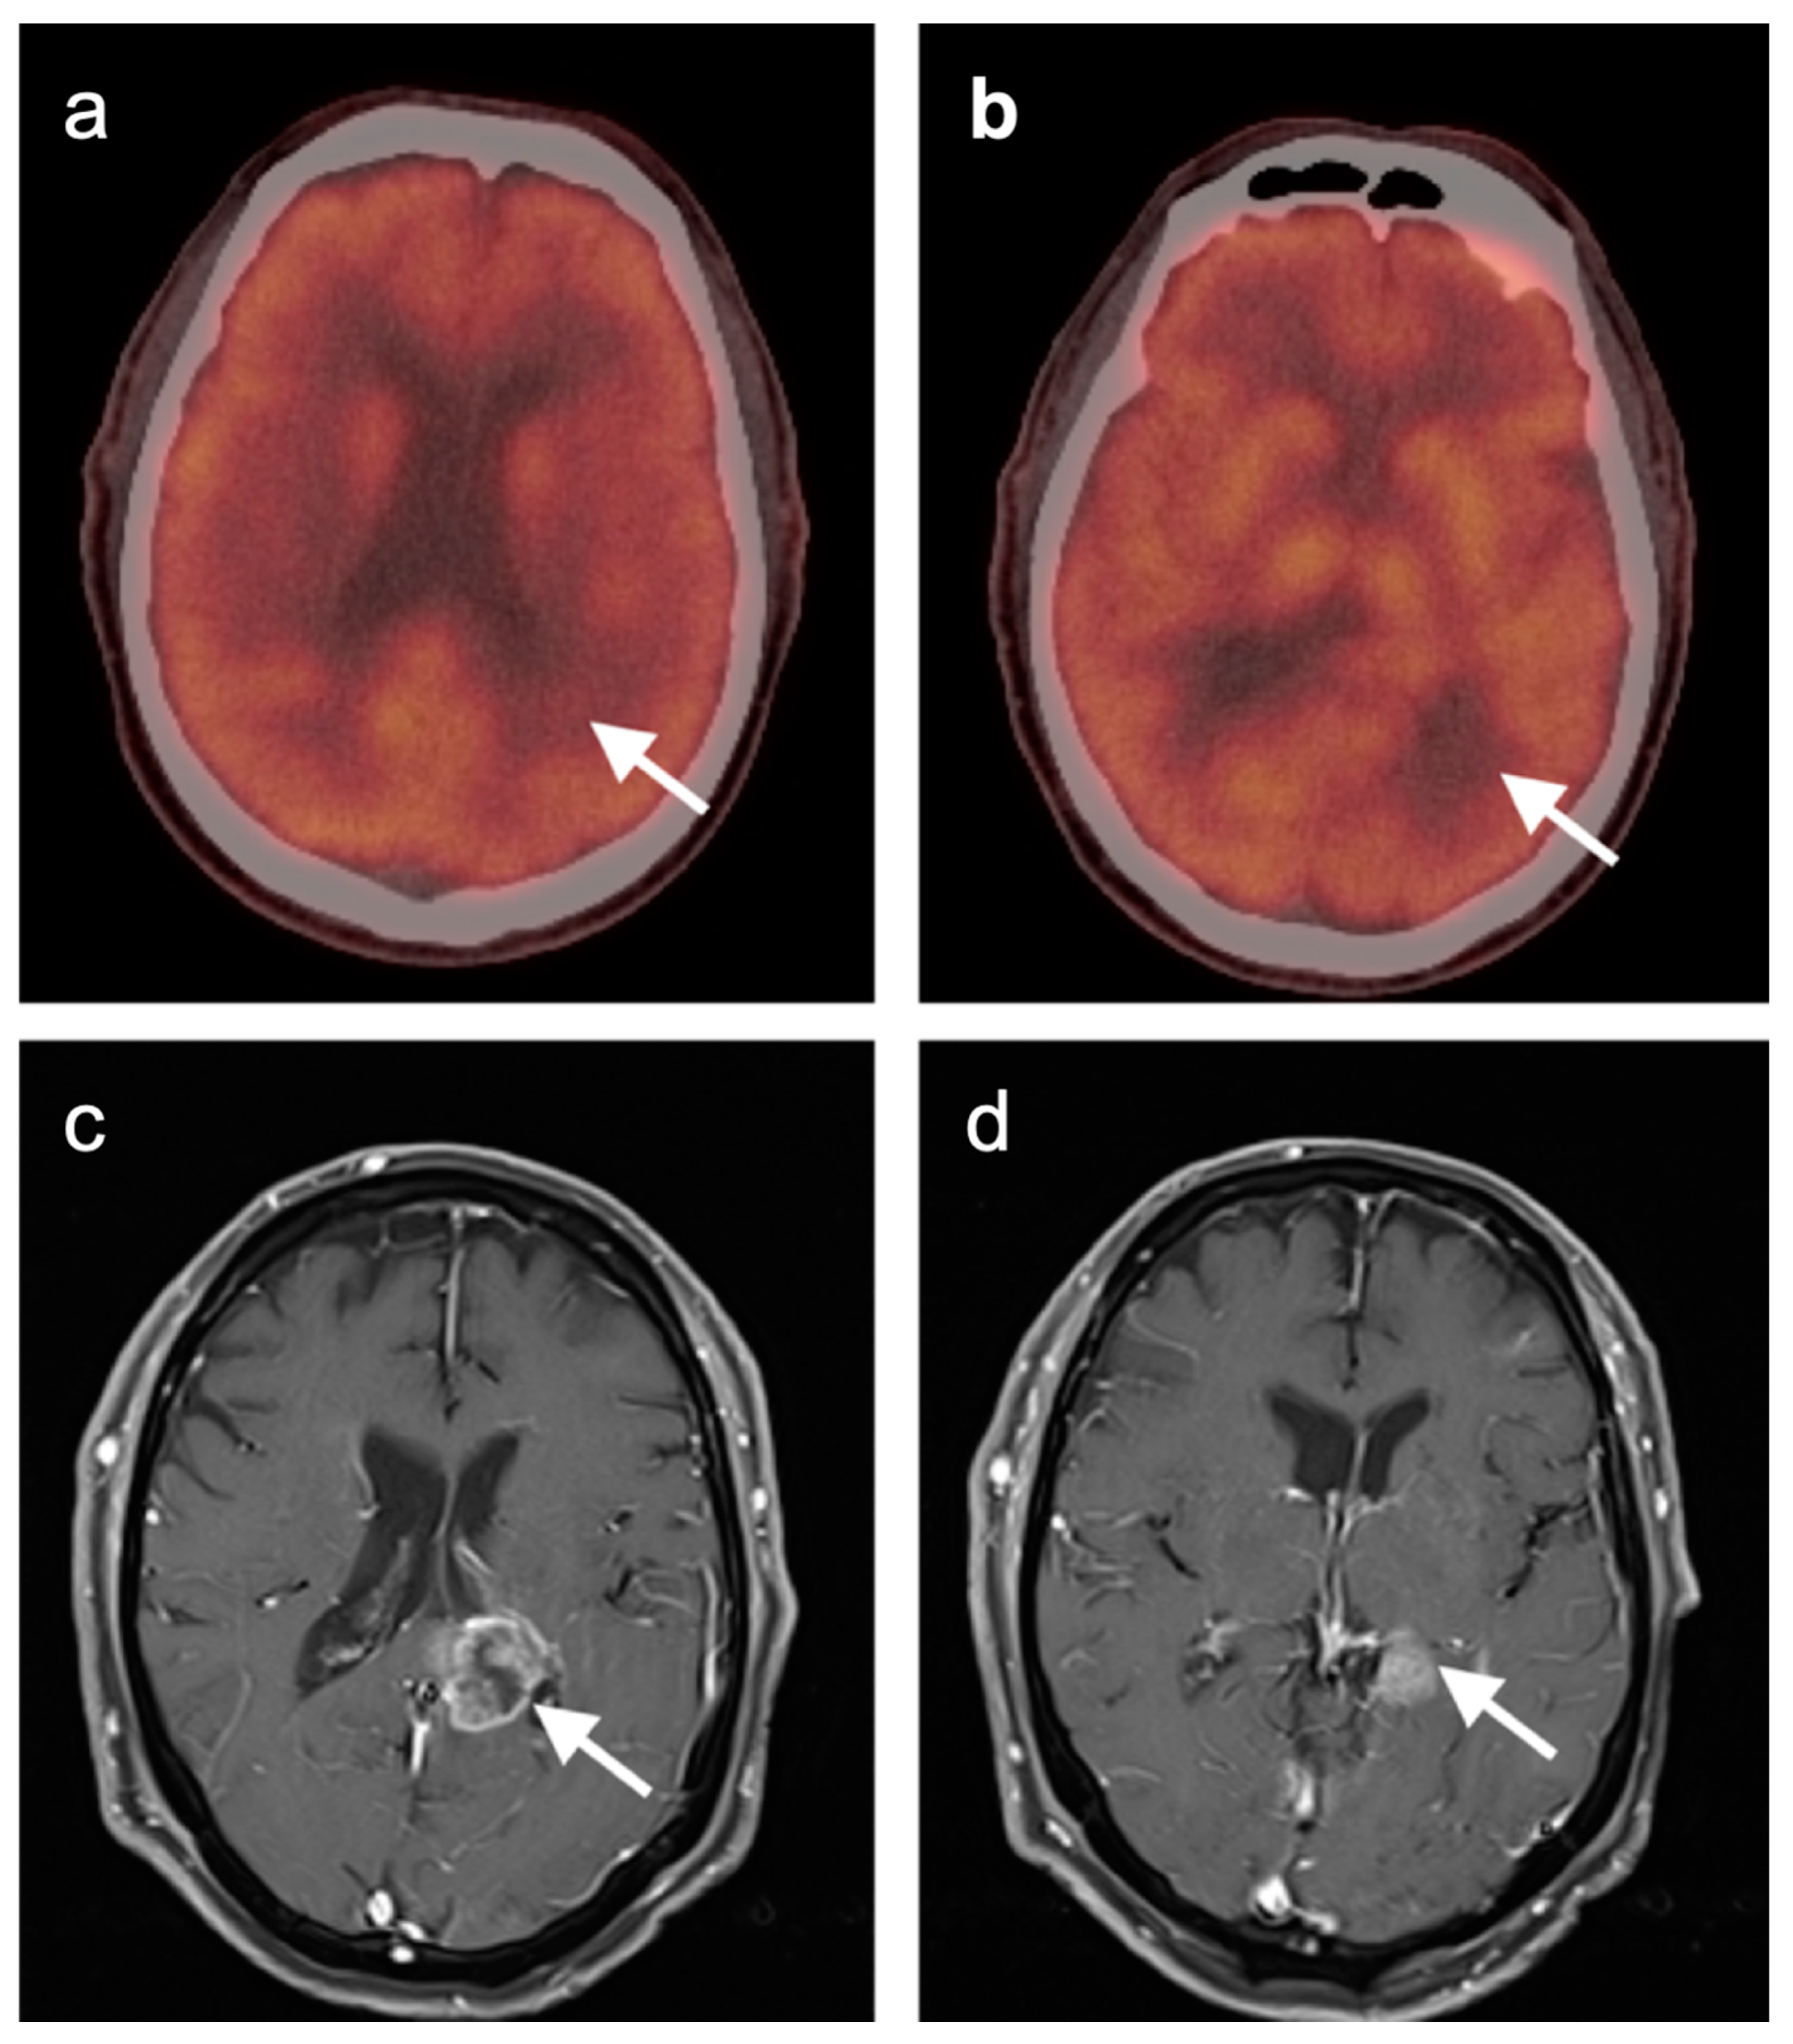

3.6. Response to Therapy

3.7. Meningioma